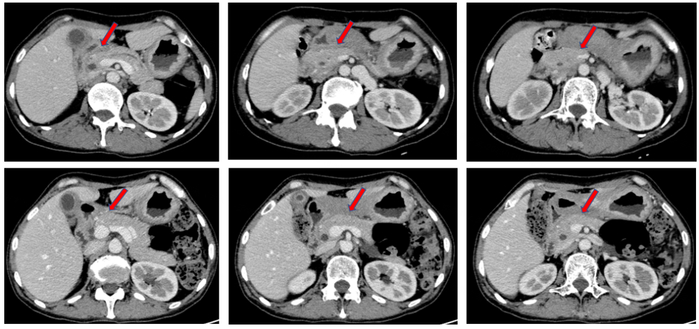

患者术后继续行4周期呋喹替尼+白蛋白紫杉醇维持治疗,期间复查肿瘤标志物及常规检验,提示:血红蛋白明显升高至正常值,抗原242(CA242)平稳下降,甲胎蛋白(AFP)显著下降。

病例总结

该病例为一位老年女性,因上腹疼痛1年,加重伴黑便一周就诊于胃肠外科,初步诊断为胃低分化腺癌(cT4N3M0 Ⅲ期)。经过MDT讨论,患者接受SOX方案转化治疗2周期,疗效评估为SD。由于治疗效果不佳(TRG评估提示TRG3,肿瘤无退缩),患者再次经过MDT讨论后更改转化治疗方案为呋喹替尼+白蛋白紫杉醇,治疗2周期后疗效评估为PR,TRG评估提示TRG2。转化治疗后患者诊断为胃低分化腺癌(ycT3N1M0 ⅡB期),经过胃肠外科评估后,行LATG术。患者术前经过转化治疗后获得5个月的无进展生存期(PFS),术后患者继续接受4周期呋喹替尼+白蛋白紫杉醇维持治疗(图7)。